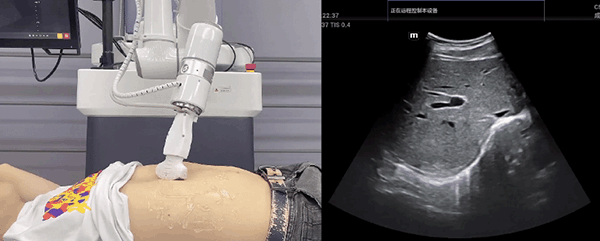

艾利特機器人末端搭載超聲探頭,可以對淺表小器官和外周血管、腹部(肝、膽、胰、腎等器官)進行超聲檢查。

普羅超聲聚焦治療機器人